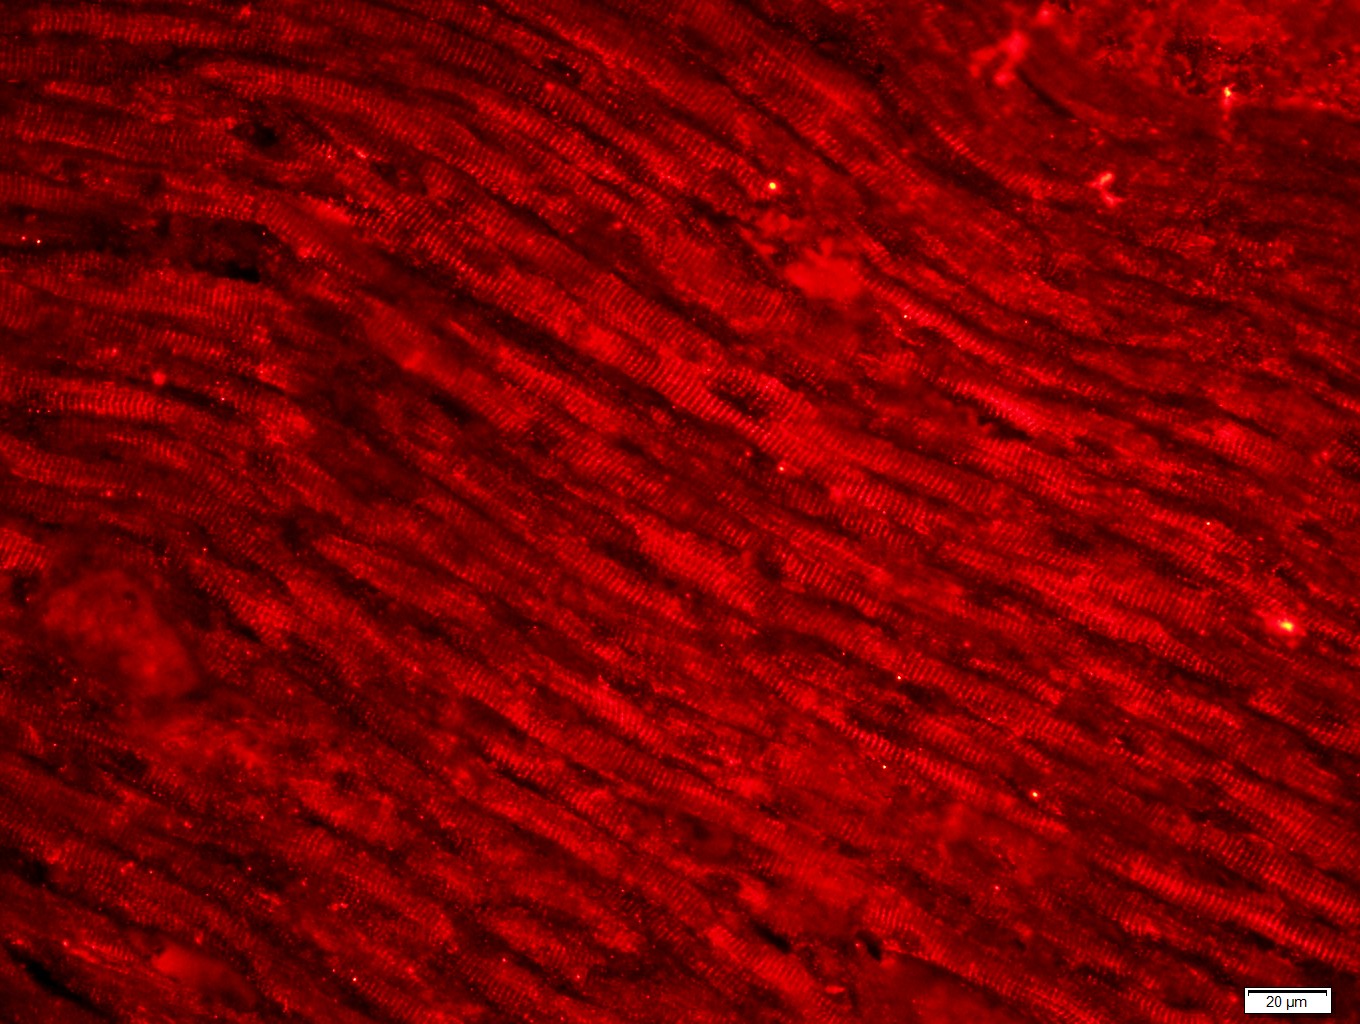

Paraformaldehyde-fixed, paraffin embedded (Rat heart); Antigen retrieval by boiling in sodium citrate buffer (pH6.0) for 15min; Block endogenous peroxidase by 3% hydrogen peroxide for 20 minutes; Blocking buffer (normal goat serum) at 37°C for 30min; Antibody incubation with (Desmin; DES) Polyclonal Antibody, Unconjugated (bs-20702R) at 1:400 overnight at 4°C, followed by a conjugated secondary antibody (bs-0295G-cy3) for 90 minutes.